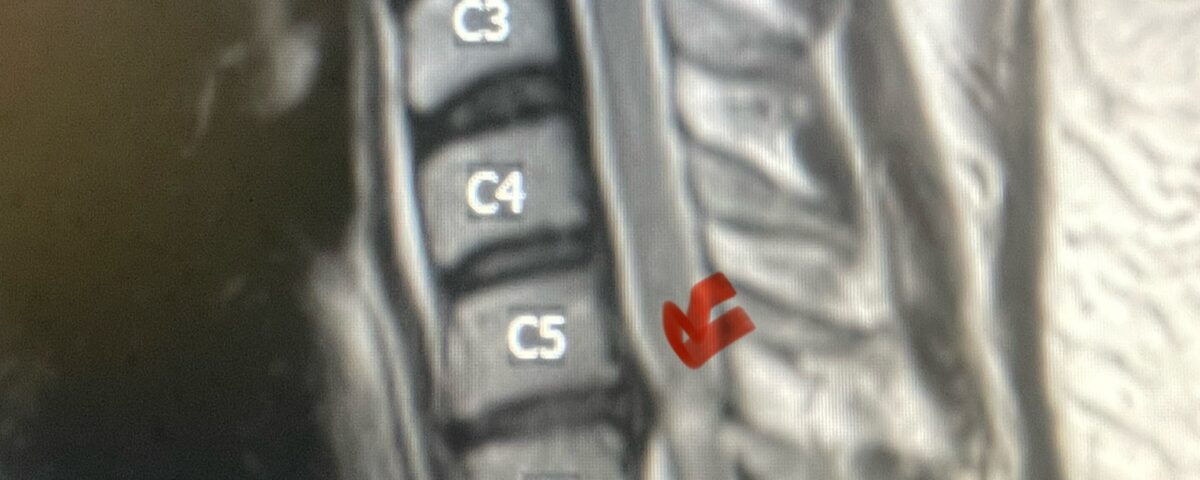

Fig 4: Sagittal T2-weighted cervical MRI demonstrating a significant disc osteophyte complex causing spinal cord compression at C 5 6 with extensive myelomalacia (red arrow)

A 37-year-old male police officer complained of a one-month history of difficulty with his balance and leg weakness. He complained of achiness in his legs. He also complained of bilateral arm weakness and numbness of his hands. He was also having difficulty writing due to the weakness. Patient had an MRI of the cervical spine which demonstrated a disc/osteophyte at C56 causing spinal cord compression and concurrent myelomalacia (Fig. 3). Patient underwent an anterior cervical discectomy with a cage and plate (Fig. 4). He tolerated the procedure well with improved numbness and weakness. This is a young person with fairly extensive myelomalacia and a fairly rapid development of symptoms. For this it was felt surgery was indicated. How he will do will depend on how much of his symptoms was caused by the compressive component or intrinsic damage to the spinal cord. As a rule, patients generally improve to some extent quickly; but their recovery of their spinal cord function can sometimes take up to 2 years to realize the extent of their improvement. Patients have to be patient with themselves in terms of their expected recovery.

Fig. 3: Sagittal T2-weighted cervical MRI demonstrating a significant disc osteophyte complex causing spinal cord compression at C 5 6 with extensive myelomalacia (red arrow)